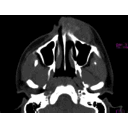

eye orbit.jpg

maxillary neoplasm.jpg

nasal cavity.jpg

paranasal sinuses.jpg